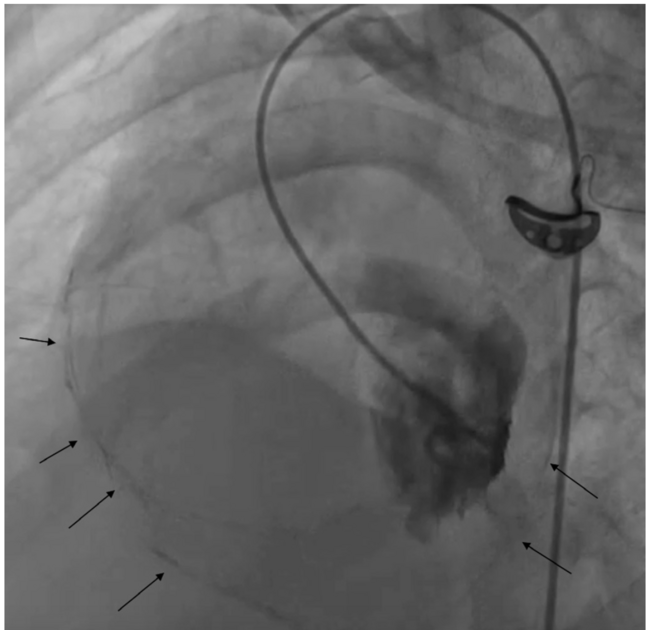

A 14-year-old boy presented with dyspnea on exertion and easy fatiguability for 1 year. He also had an episode of pedal edema 6 months prior, which resolved with diuretics. He had a history of tuberculosis treated with a 6-month course of antitubercular therapy. On examination, he had a loud pulmonary component of second heart sound and an added heart sound. Jugular venous pressure was elevated. After echocardiography, the patient was taken for cardiac catheterization. A left ventricular angiogram was performed during catheterization (Figure 1 and Video 1). The left ventricular angiography showed mild reduction in ventricular systolic function. On detailed analysis, it is evident that longitudinal contraction of the left ventricle is preserved, whereas the circumferential contraction is severely impaired. Pericardial calcification also can be seen encircling the left and right ventricles (Figure 2). Echocardiography showed that the patient had moderate pulmonary hypertension and features suggestive of constrictive pericarditis. In restrictive cardiomyopathy, the longitudinal contraction is impaired whereas the circumferential contraction is preserved. In dilated cardiomyopathy, the left ventricle is dilated. There is obliteration of the left ventricular cavity during systole in cases of hypertrophic cardiomyopathy. Pericardial calcification is evident in around 25% of cases of constrictive pericarditis and predominantly seen in those with tubercular and pyogenic etiology. The subepicardial myocardial fibers are responsible for radial shortening and subendocardial fibers are responsible for longitudinal shortening. In constrictive pericarditis, the involvement of the subepicardial fibers leads to reduction in the circumferential shortening. The patient was referred for pericardiectomy.